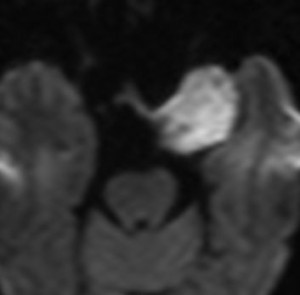

小脳類皮のう胞

偶然発見された女の子のものです。左のCTで石灰化があります。右の拡散強調画像 DWI で白く高信号に描出されるのが特徴です。手術では腫瘍内部に毛髪がたくさんありました。後下小脳動脈に強く癒着していて,脳軟膜からの剥離もできませんでしたが,完全摘出しました。無症状でも”完全”摘出 complete removal するべきです。